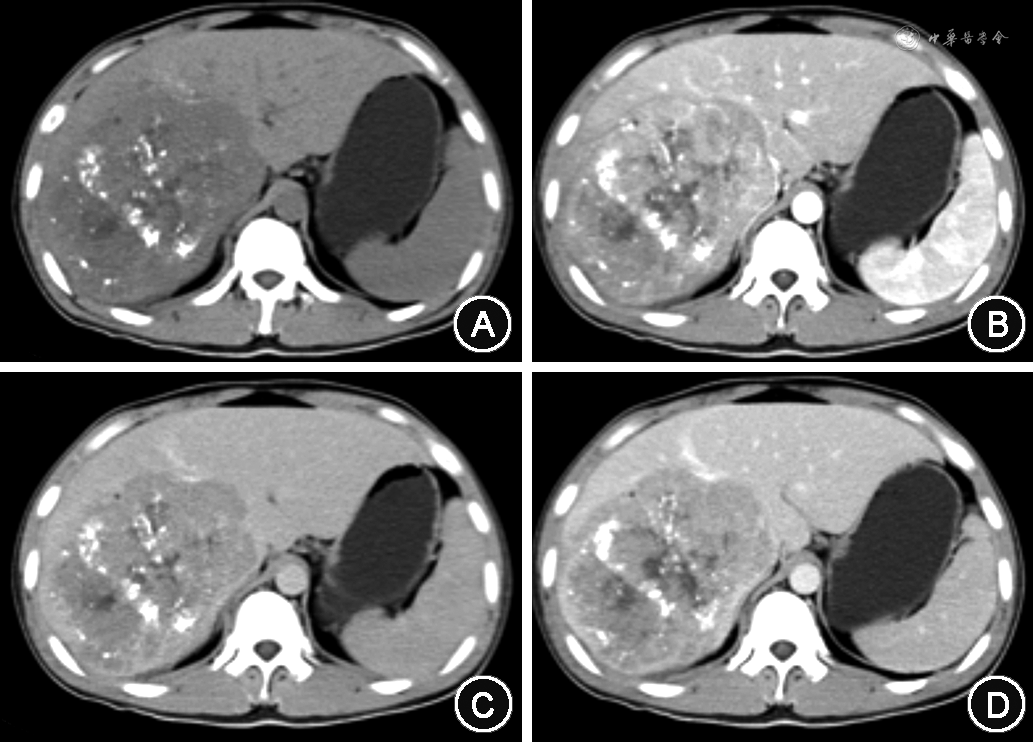

2. 影像学检查:22例行超声造影检查示肝内单发或多发高回声实性占位均提示肝细胞癌;13例行正电子发射计算机断层显像(positron emission tomography-computed tomography,PET-CT)检查,其余16例行CT检查,1例诊断为胆管细胞癌,余15例为肝细胞肝癌(图1)。

cHCC-CC是一种较为少见的肝脏恶性上皮性肿瘤,大致占原发性肝癌的0.4%~14.2%[1]。多项研究表明,cHCC-CC更多表现为肝细胞癌的临床特征[2, 3]。如(1)患者多为中、老年;(2)以男性多见;(3)常伴乙型或丙型肝炎病史;(4)多合并有肝硬化;(5)常伴血清AFP的升高;(6)早期侵犯门静脉和肝静脉,出现血道转移;(7)部分病例可伴有肝内卫星灶。本组病例与文献报道基本一致。影像学可单独或兼有肝细胞癌的“快进快出”或胆管细胞癌的“慢进慢出”强化方式,增强模式是否与肿瘤成分所占比例有关仍存在争议[4, 5]。30例影像检查可见明确的占位,多诊断为肝细胞癌,均与组织学诊断不一致。影像学检查对术前明确诊断无意义,但对发现病变具有重要的价值。